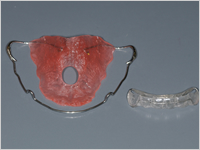

治療を終了出来る段階になると、歯に固定しているブラケットを取り外す前にはずした後に付けていただく保定装置を作るための型を採って準備します。

治療を終了出来る段階になると、歯に固定しているブラケットを取り外す前にはずした後に付けていただく保定装置を作るための型を採って準備します。 - 動的矯正治療の終了

年に3~4回くらい来院していただき、かみ合わせの具合、歯ブラシの状態や、保定装置をチェックして、経過を観察します。

年に3~4回くらい来院していただき、かみ合わせの具合、歯ブラシの状態や、保定装置をチェックして、経過を観察します。 - 定期メンテナンス